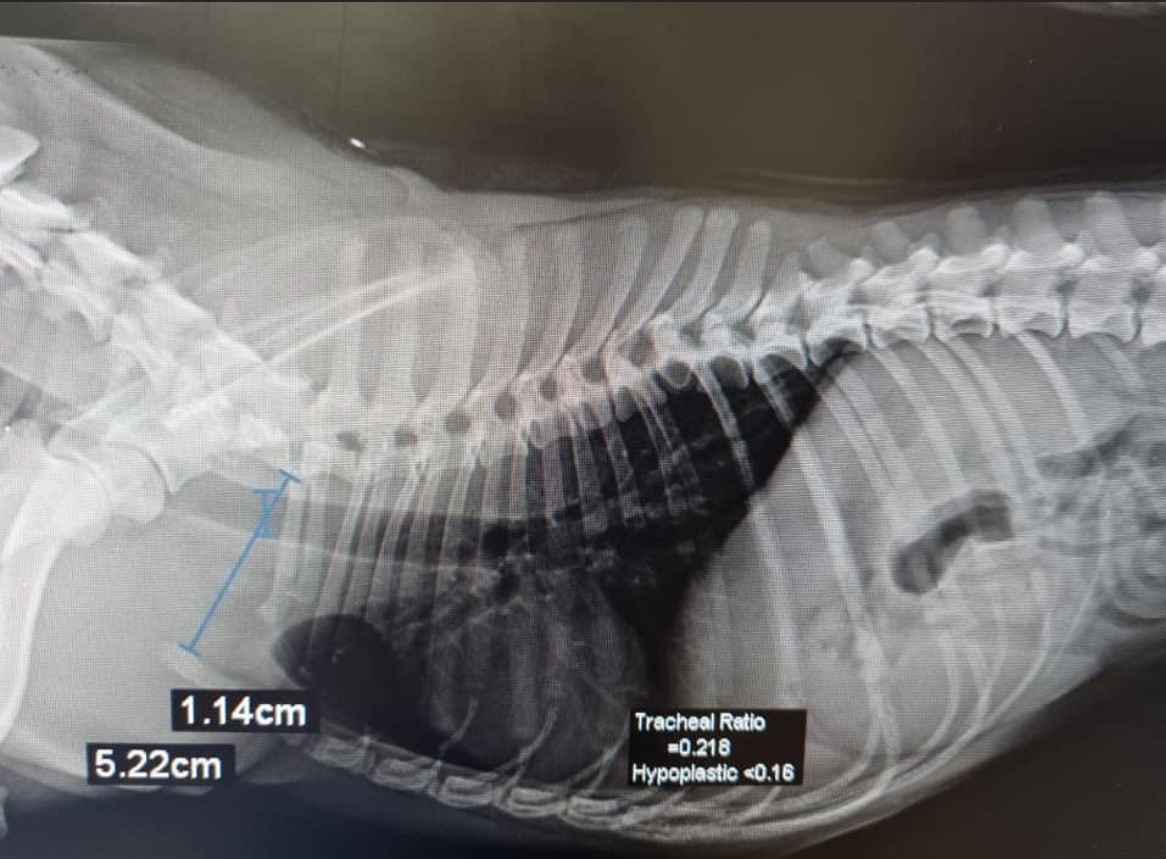

From melbournebulldogclinic.com.au

Hypoplastic Trachea Melbourne Bulldog Clinic Soft Dog Collar Trachea How to treat tracheal collapse in dogs. Tracheal collapse (ie, reduction in tracheal lumen diameter) is characterized by the flattening of the tracheal rings with laxity or redundancy of the. Your vet will assess your. Diagnosis is made by performing a thorough clinical exam initially. Tracheal collapse is a progressive respiratory condition that occurs when these tracheal rings of cartilage. Soft Dog Collar Trachea.

Hypoplastic Trachea Melbourne Bulldog Clinic Soft Dog Collar Trachea A collapsed trachea occurs when these rings weaken and flatten, making it hard for air to get through and causing breathing difficulties for your dog. This condition is most commonly. Your vet will assess your. Tracheal collapse is a progressive respiratory condition that occurs when these tracheal rings of cartilage collapse. Tracheal collapse (ie, reduction in tracheal lumen diameter) is. Soft Dog Collar Trachea.